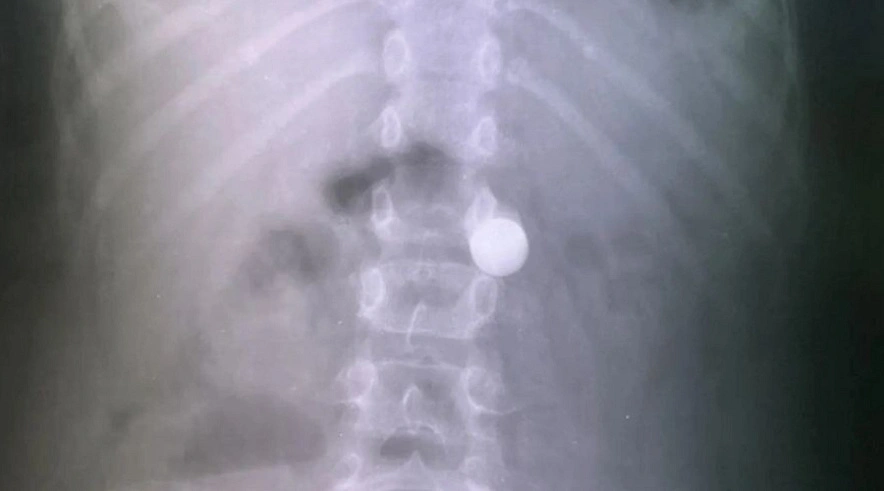

Во время новогодних праздников врачам в Балаково пришлось спасать мальчика, проглотившего крупный металлический шар. И, по словам медиков, это стало рекордом последних лет, поскольку за все длинные выходные это оказался единственный случай попадания внутрь человека постороннего предмета.

В Балаковской городской клинической больнице (БГКБ) рассказали, что обычно в новогодние праздники в приемный покой попадает немало пациентов, как детей, так и взрослых, которые случайно или по неосторожности проглатывают различные посторонние предметы, которые приходится извлекать. Однако 2026 год стал исключением, и в БГКБ попал только 8-летний мальчик, проглотил увесистый металлический шарик диаметром в целый сантиметр. И тот факт, что для врачей-эндоскопистов после новогодних праздников оказалось так мало работы, приятно удивил работников БГКБ.